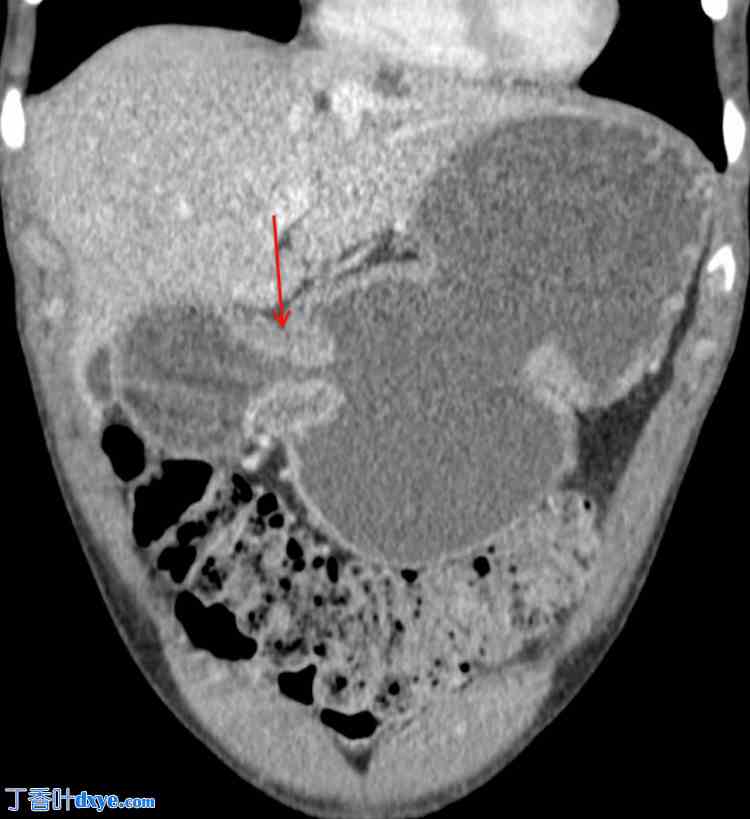

术后第二天,患者出现恶心、呕吐和腹胀。CT 扫描显示腹部中央、肠系膜内、手术吻合口近端存在小肠闭环梗阻(图 2、3)。这提示可能存在内疝或其他术后并发症。

图 2. 腹部及盆腔增强 CT(冠状位)显示小肠管弥漫扩张,结肠基本减压,吻合口附近可见过渡区(红色箭头)。过渡区代表正常口径肠管向扩张肠管过渡的点,指示梗阻部位,是确定潜在病变位置的关键发现。